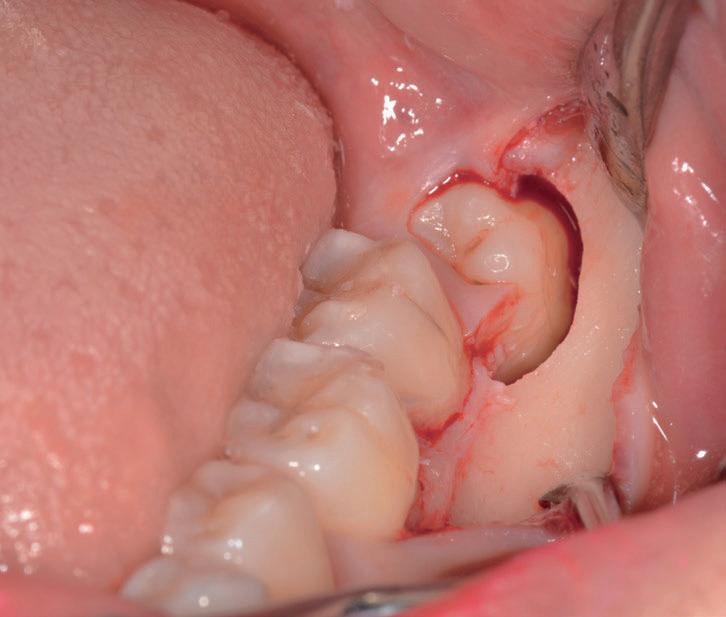

L’estrazione di un dente del giudizio incluso orizzontalmente, sfruttando questa tecnica con il manipolo dritto, richiede un’ulteriore rimozione di struttura dentale e di osso. Figg. 180-183

Per questo motivo, il lembo deve essere esteso fino al primo molare e bisogna avere una visione del sito chirurgico adeguata. Più il dente è inclinato orizzontalmente più la rimozione di osso vestibolare è necessaria.

Solitamente viene utilizzata una fresa a fessura dritta da manipolo per sezionare le radici, ma è preferibile usare una fresa rotonda laddove c’è la necessità di rimuovere l’osso alveolare attorno alla corona, come mostrato in fotografia. Figg. 184-187

In questo caso la separazione del periostio e la rimozione di osso vestibolare è quasi inevitabile per estrarre il #38.

Figg. 180-187 - Un caso di un’estrazione di un dente del giudizio, utilizzando il manipolo dritto. Fig. 180 Fig. 181 Fig. 182 Fig. 183 Fig. 184 Fig. 185 Fig. 186 Fig. 187